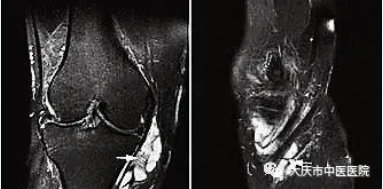

4.磁共振成像(MRI)可评估膝关节病理和排除替代诊断。